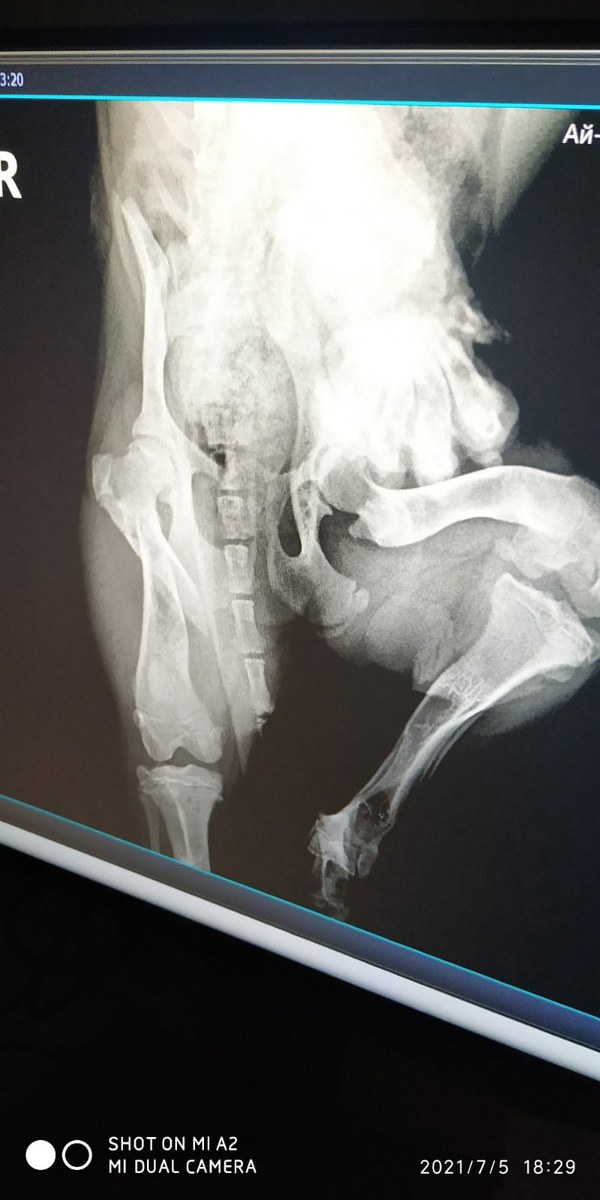

Микро девочка Мэри сломала лапку.

Мы с Мэри записались на очередной осмотр травматолога по поводу деформированных передних лапок, но за день до приема она травмирует лапку!!!

Доктор осмотрел, сделали рентген и обнаружил перелом бедренной кости.

Добегалась девочка, получила перелом.

В пятницу операция на которую надо 80000-10000р., будут устанавливать пластину.🙄